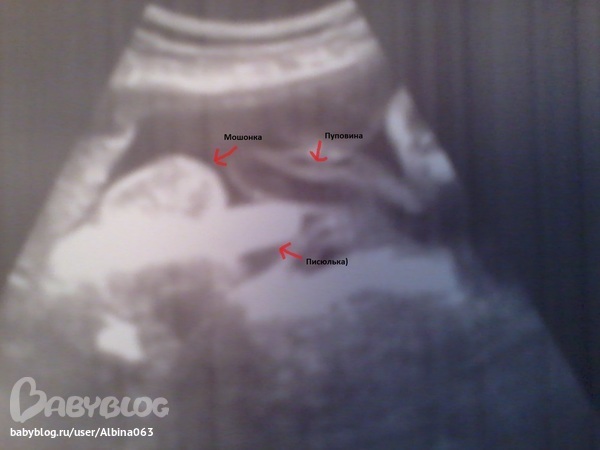

Врач УЗИ такая милая смешная женщина, приложив датчик к пузу, без раздумий сказала, что у вас мальчик.

Показала машонку, сказала что яички уже опустились в мошонку (а они что могут и не опуститься), потом показала писюн...и удивленно сказала ого...вот это достоинство...сделав пару фото, сказала что бы обязательно показала их папе, пусть тот гордиться

Приехав домой, показала фото писюльки мужу, надо было видеть его реакцию)))) ОГО..что такой большой...может это грыжа...нет это точно грыжа...

Я...сам ты грыжа...было бы что то не так врач сказала бы))))